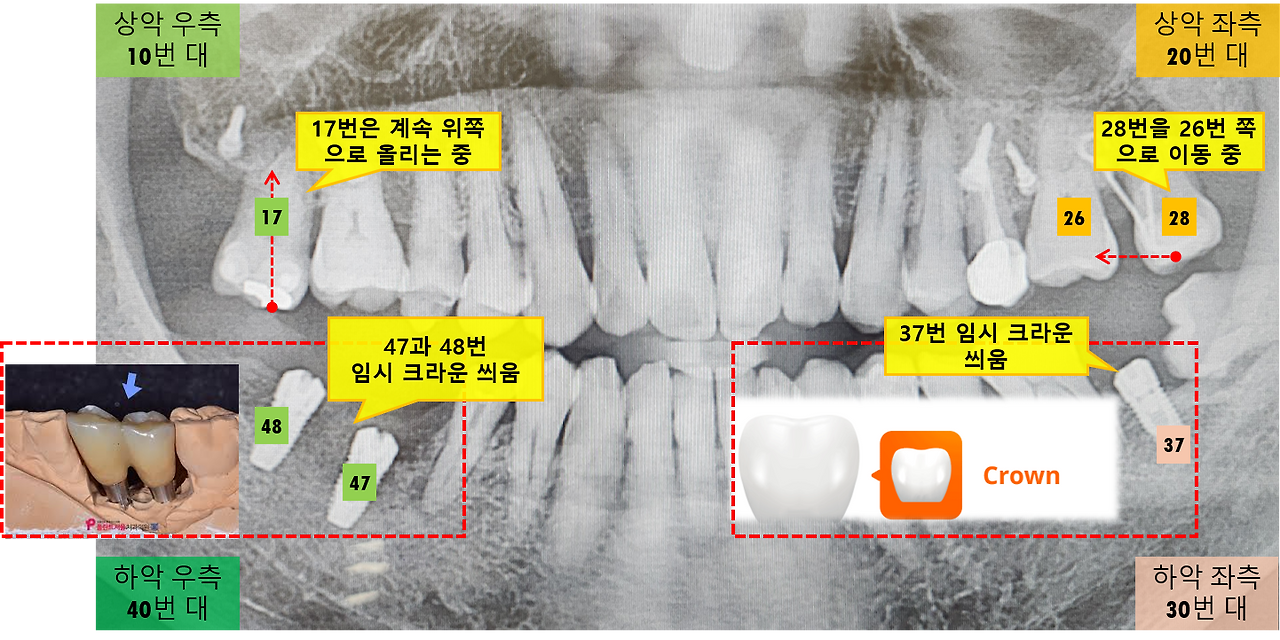

지난번 37번 치아에 임시 크라운을 씌운 후, 맞물리는 위쪽 28번 치아와의 교합 과정에서 상당한 불편함이 있었습니다. 오랜 시간 동안 아래 치아와 맞물리지 않아 저작 자극을 받지 않다가, 갑자기 교합력이 가해지면서 통증이 5일 정도 지속됐던 것으로 기억되네요. 물론 개인에 따라 통증의 정도와 기간은 달라질 수 있을 것입니다.

이번에 임시 크라운을 시술한 곳은 오른쪽 47번과 48번 치아입니다. 저는 각 임플란트마다 크라운을 씌우는 줄 알았는데, 두 개가 연결된 형태의 크라운을 사용했더군요. 이게 임시 크라운이라서 그런 것인지, 아니면 두 개를 동시에 씌우는 것이 잇몸뼈에 부담을 줄이고 심미성을 높이기 위해서인지는 모르겠네요.

임시 크라운을 장착 후 입을 닫아보니 17번 치아와 많이 부딪히는 상황이라, 수차례 임시 크라운의 일부를 세밀하게 갈아내는 작업이 반복되었습니다. 교합지를 넣고 이를 악물고 좌우로 갈아보며 정밀하게 교합 상태를 확인했고, 적절한 높이가 확인된 후 임시 크라운을 접착제로 붙이는 것으로 오늘의 시술은 모두 완료되었네요.

걱정했던 것보다 위쪽 치아의 통증은 그리 심하지 않습니다. 아마 교정 장치를 통해 위쪽으로 치아를 올리는 과정을 지속해 온 덕분에 잇몸이 어느 정도 자극에 익숙해진 덕분이 아닐까 싶네요. 다만, 좀 단단한 음식을 씹으면 약간의 통증 또는 불편함이 느껴지기는 하지만 그래도 식사하는데 불편함은 없네요.

이제 교정 중인 17번 치아가 점차 위쪽으로 올라가면 거기에 맞춰 47, 48번 임시 크라운의 높이도 맞춰갈 예정이라고 합니다. 치료기간이 얼마나 더 시간이 소요될지는 알 수없지만, 단계별로 차근차근 진행이 되어가는 과정을 보니 마음이 한결 놓이고 기분도 좋아지네요.

다음 진료 때는 먼저 시술했던 임시 크라운을 씌운 37번 치아가 26번 치아와 교합이 잘 되는지를 확인한다고 하네요.